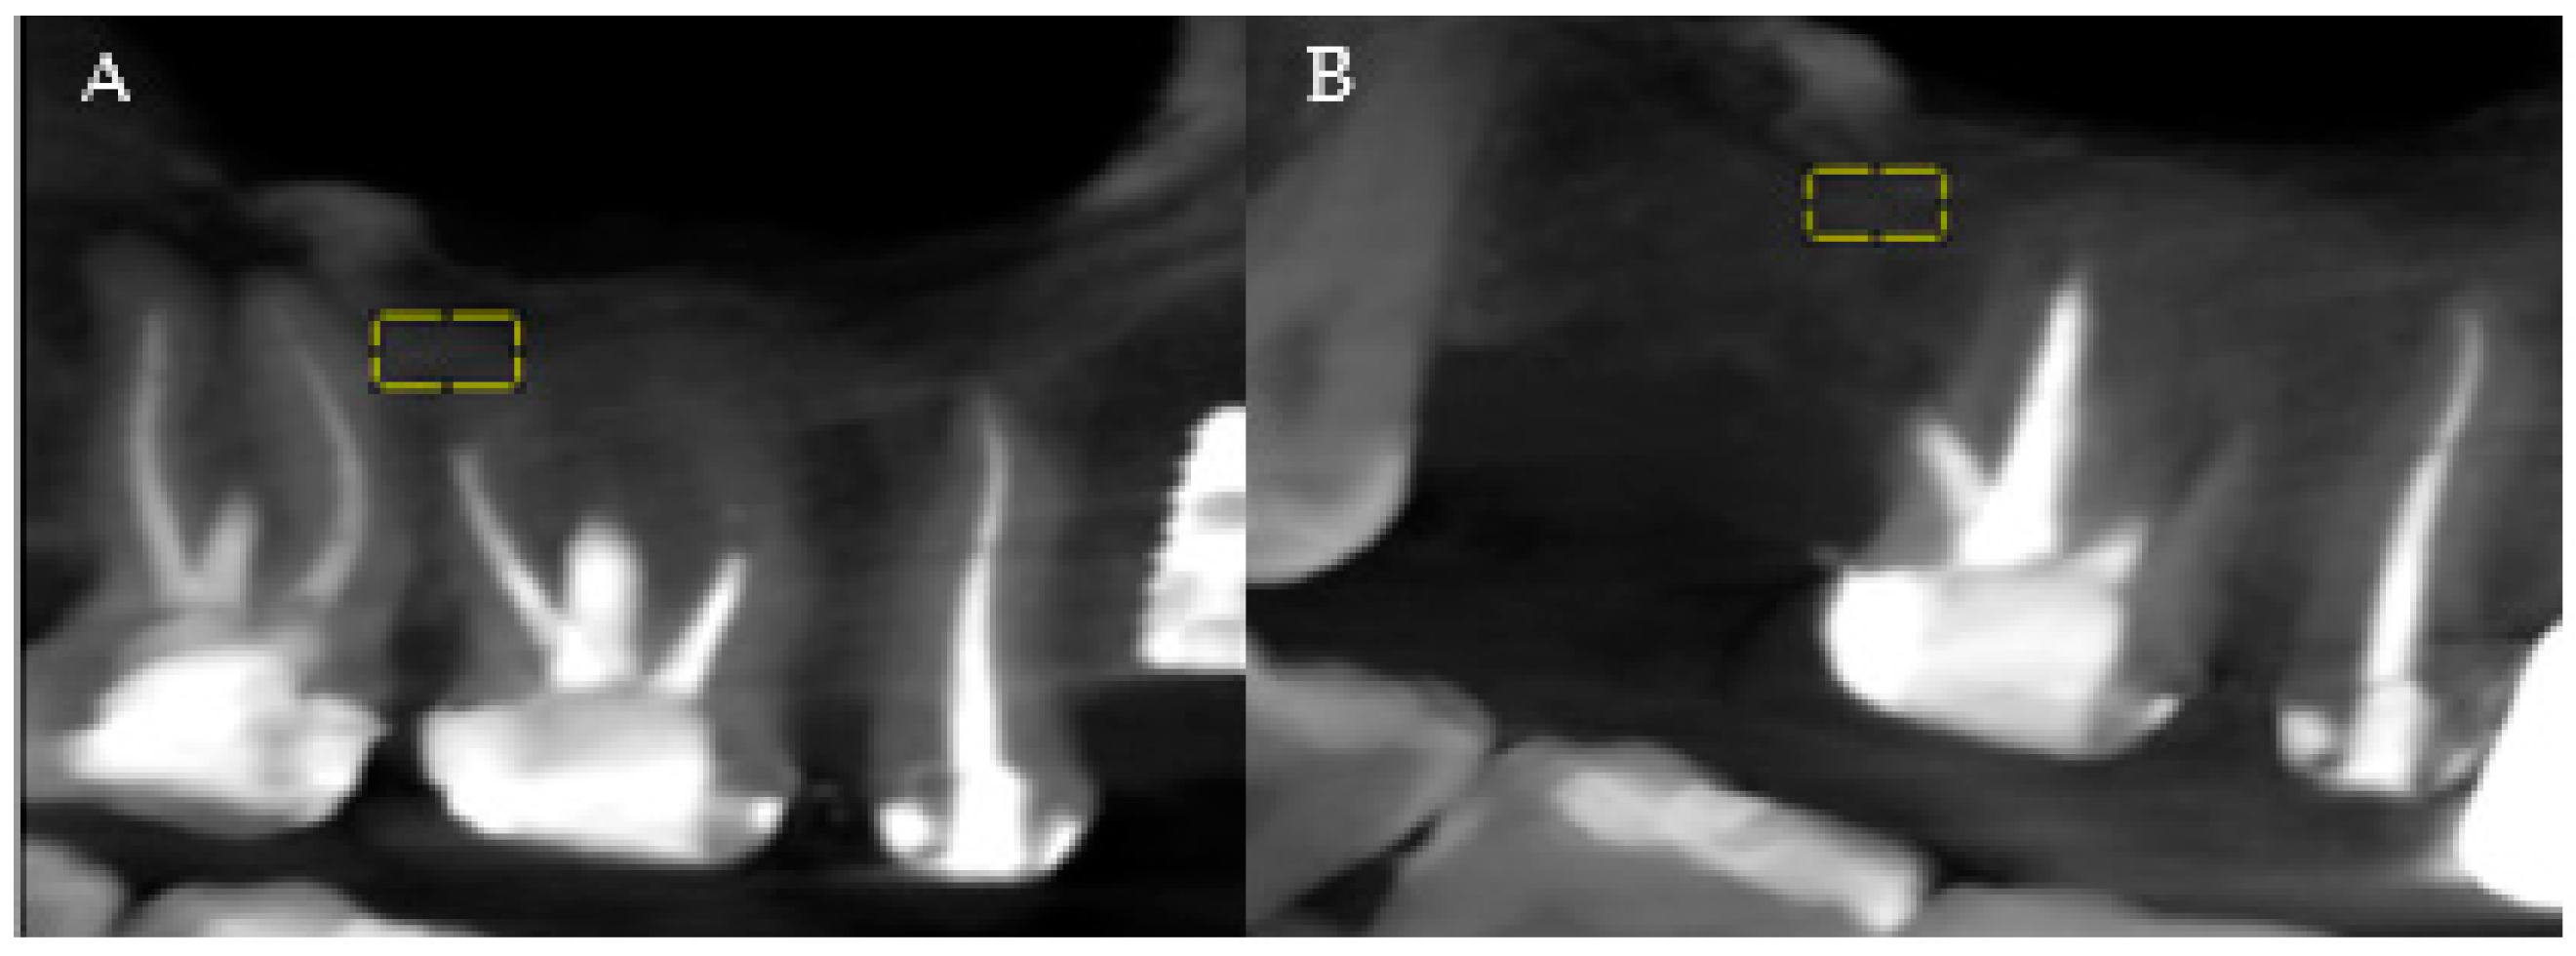

The analysis of the patients’ CBCTs from the pre-and post-extraction stages to place a dental implant was performed with both imaging software and ImageJ software (National Institutes of Health (NIH)). The precise comparison of the data obtained before and after the surgical intervention was achieved by choosing stable reference points on anatomical formations that do not change their size immediately post-extraction. At the level of the maxilla, the analysis was related to the maxillary sinus, and at the level of the mandible, the analysis was referred to the mandibular canal (Figure 1A,B, areas of interest). Measurements were performed for all three planes provided by the CBCT analysis: vertical, sagittal, and transversal.

Figure 1.

(A) Maxillary CBCT—before extraction. (B) Maxillary CBCT—after extraction. Yellow = areas of interest.